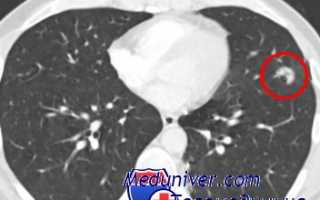

Весьма актуальной является задача организации дальнейшего медицинского обслуживания больных с нетуберкулезной патологией, выявляемых в результате комплексного дифференциально-диагностического обследования туберкулезными учреждениями. Наиболее сложной является организация лечения больных с опухолями легких и хроническими воспалительными заболеваниями. Здесь существуют самые разноречивые мнения.

Одни высказываются за передачу наблюдения и лечения больных с неспецифическими воспалительными заболеваниями легких противотуберкулезному диспансеру, другие придерживаются диаметрально противоположной позиции, предлагая передавать всех больных с нетуберкулезной патологией в ведение поликлиник. Мы считаем, что тесный и деловой контакт флюорографической службы и туберкулезных учреждений позволит увеличить процент больных, выявляемых Бранней стадии заболевания.

В Центральной туберкулезной больнице за последние 5 лет прооперировано 174 больных но поводу рака и 128—по поводу хронических неспецифических пневмоний, абсцессов и ограниченных бронхоэктазов. При злокачественных заболеваниях 95% оперированных выписано в удовлетворительном состоянии; при неспецифических воспалительных заболеваниях легких— 96%.

image

Активная хирургическая деятельность по лечению хронических неспецифических воспалительных заболеваний легких и рака легкого у больных, находящихся в туберкулезных стационарах, по нашим данным, ни в коей мере не снизила активности в хирургическом лечении больных туберкулезом.